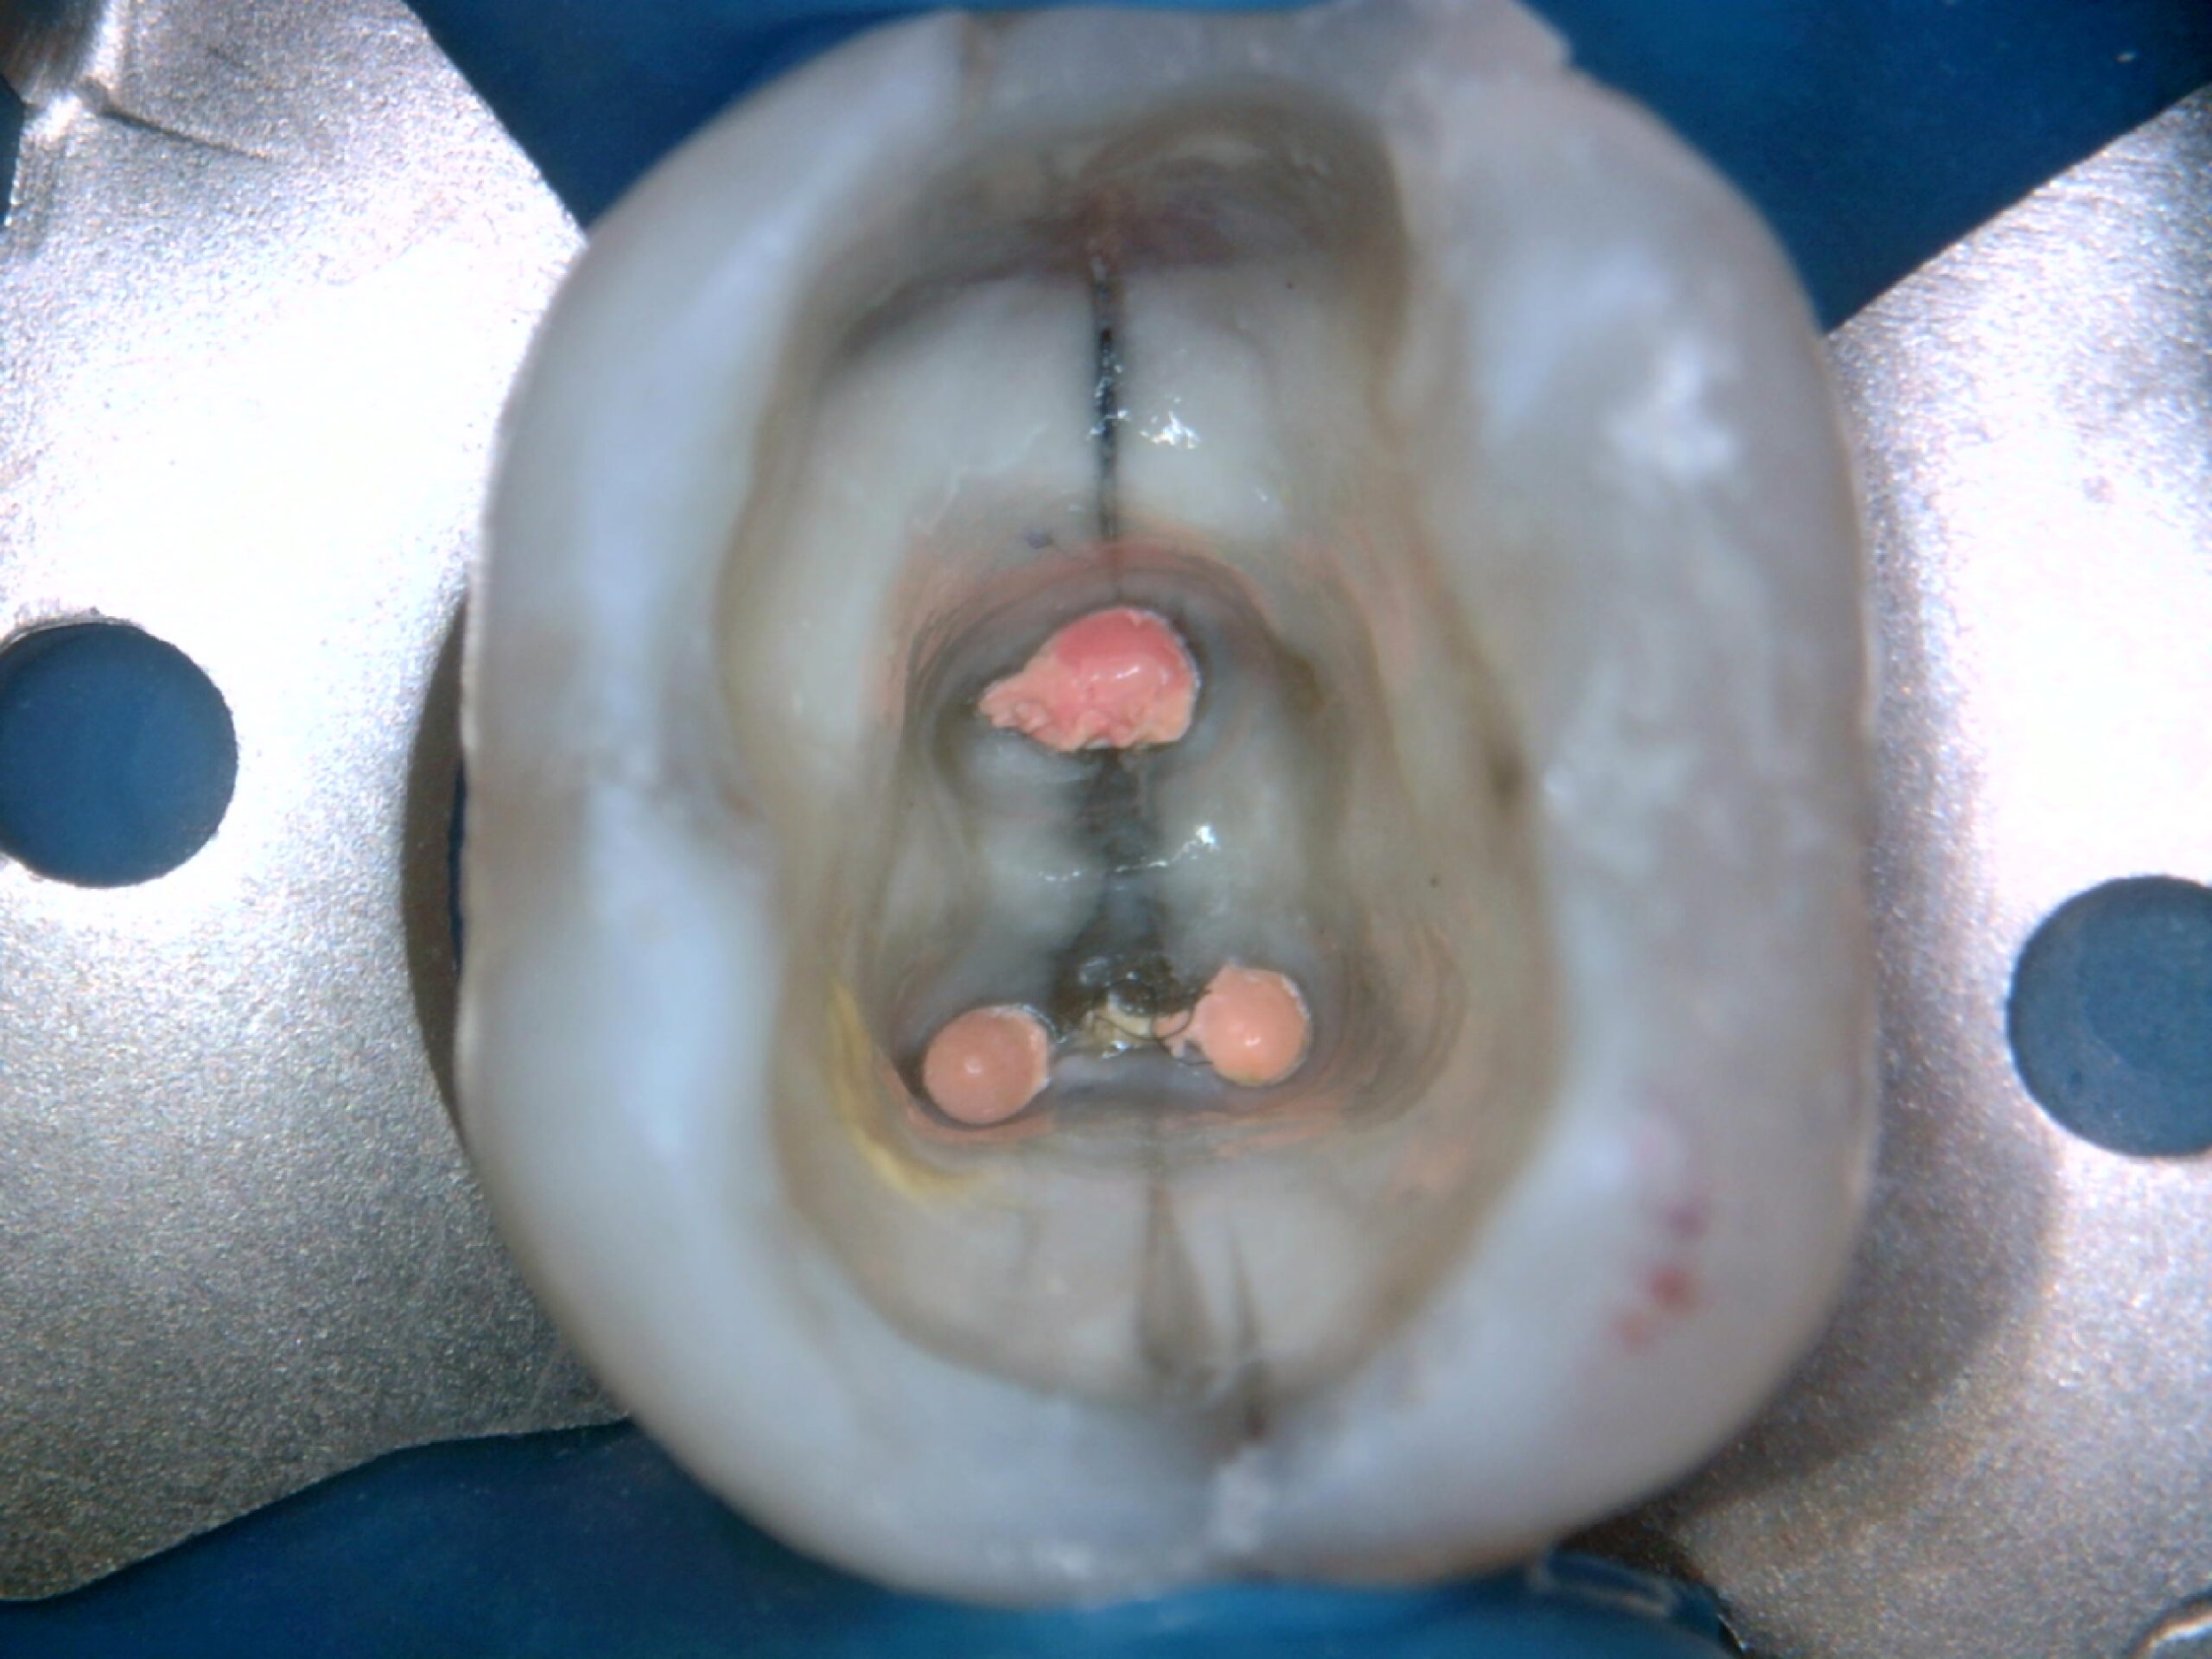

Perfurações, desgaste e anatomia interna visível na abertura do dente

3. Documentação completa do processo endodôntico

Desde o pré-operatório até o pós, tudo fica registrado com nitidez.

Exemplos reais de uso da SkyCam na Endodontia